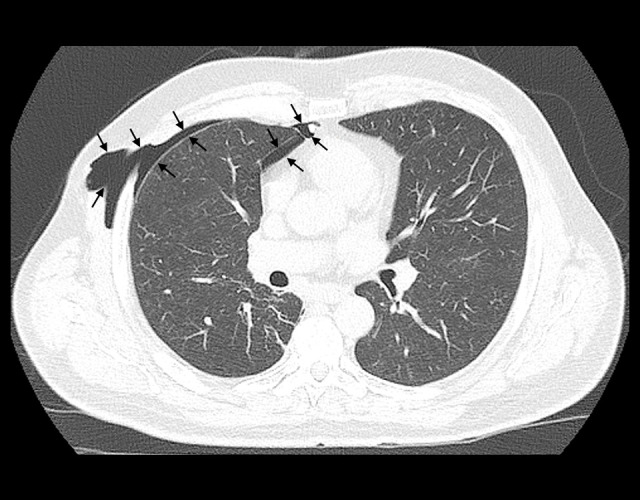

背景胸腔镜解剖肺切除术后,胸壁疝和残余胸膜间隙是已知的并发症。一些胸壁疝的危险因素已被描述;然而,残余胸膜间隙从未被描述为其中之一。我们报告的2例病例表明,术后残留的空气空间可能是胸壁疝的一个新发现的危险因素。病例报告:病例1:一名71岁男性在三孔胸腔镜下左下肺叶切除术治疗早期非小细胞肺癌1周后,在第4肋间切口处发生胸壁疝。他没有任何已知的术后胸壁疝的危险因素,但他的术后过程因残余胸膜间隙而复杂化。病例2:一名60岁男性,因早期非小细胞肺癌行三孔胸腔镜右根尖上叶节段切除术5个月后,在第四肋间切口术后出现胸壁疝。未发现术后胸壁疝的危险因素;然而,她的术后过程也因残余胸膜间隙而复杂化。结论胸膜残留气体通过胸腔镜切口可能阻碍伤口愈合,有利于胸壁疝的发生。在有风险的患者中采用视频辅助胸外科切口闭合技术可能有助于预防术后胸壁疝。这些病例强调了残留胸膜间隙可能是术后胸壁疝的一个新发现的危险因素,并提出了潜在的预防措施。

BACKGROUND Chest wall hernia and residual pleural space are known complications after thoracoscopic anatomical lung resection. Some risk factors for chest wall hernia have been described; however, residual pleural space has never been described as one of them. We present 2 cases suggesting that postoperative residual air space can represent a newly identified risk factor for chest wall hernia. CASE REPORT Case 1: A 71-year-old man developed a postoperative chest wall hernia at the fourth intercostal incision level 1 week after a 3-port thoracoscopic left lower lobectomy for early-stage non-small cell lung carcinoma. He was not known to have any described risk factors for postoperative chest wall hernia, but his postoperative course was complicated by a residual pleural space. Case 2: A 60-year-old man developed a postoperative chest wall hernia at the fourth intercostal incision level, diagnosed 5 months after a right apical upper lobe segmentectomy by 3-port thoracoscopy for early-stage non-small cell lung carcinoma. She was not known to have any risk factors for postoperative chest wall hernia; however, her postoperative course was also complicated by a residual pleural space. CONCLUSIONS We suggest that air flow through the thoracoscopic incision, due to residual pleural air, could impede wound healing and favor chest wall hernia. Adaptation of the closure technique for video-assisted thoracic surgery incisions in patients at risk may help prevent postoperative chest wall hernias. These cases highlight the possibility that residual pleural space could be a newly identified risk factor for postoperative chest wall hernia and propose potential preventive measures.